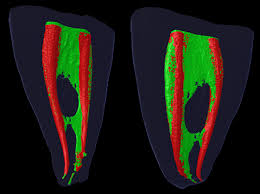

根管の中は枝分かれしていてこんなに複雑な構造をしています。

下の図のようにニッケルチタンのファイルで根管形成をしても根管内の汚物、デブリはかなり取り残すというデータがあります。

赤の部分は拡大されてファイルが届いた部分、緑は拡大されずに取り残されています。